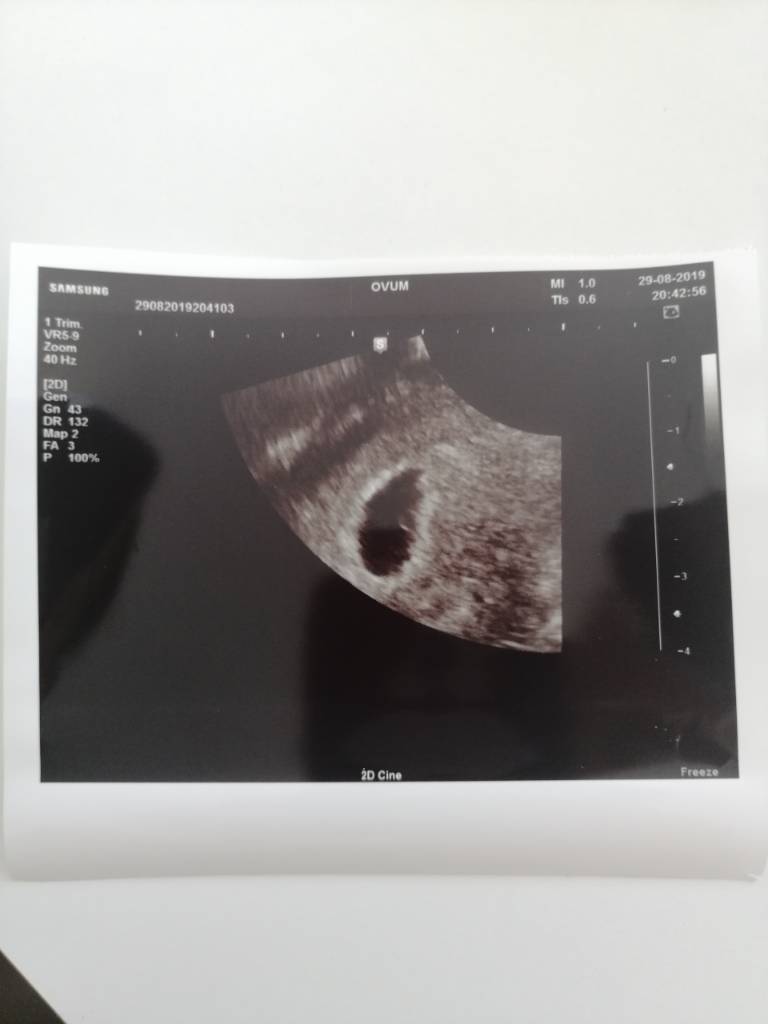

No to ja zacznę pierwsza. Wszystko ok! [emoji3526] Jest akcja serca, zero śladów jakichkolwiek krwawień. Niepotrzebna panika.